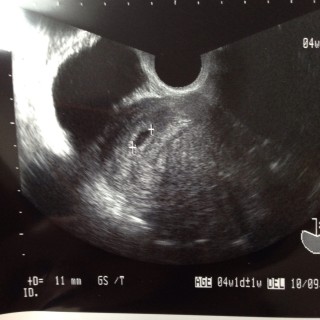

4w0dで不妊治療の病院受診。(丁度お休み周期の自然妊娠)陽性反応と血液検査で妊娠確定。5w0d11ミリの胎嚢確認で正常妊娠を確認しました。心拍が確認できたら卒業予定です。